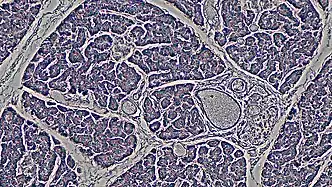

The ductal pancreas network originates from the central pancreatic duct—this main duct with the bile duct opens into the duodenum. The ductal cells of the main pancreatic duct are bound by connective tissue and produce a columnar epithelium.[3] Interlobular ducts originate from the main pancreatic duct and connect the various pancreatic lobes. In these lobes, the intercalated ducts expel acini. Meanwhile, the ductal cells of these intercalated ducts create a simple squamous epithelium that rapidly converts into simple cuboidal, and connective tissue also surrounds them.[3] As the ducts grow larger, the epithelium becomes cuboidal or columnar (when large in diameter, the ducts become stratified cuboidal), and connective tissue surrounds them. Pancreatic ductal cells are very similar to ductal cells of other exocrine glands (liver, bile duct, salivary glands).[3] Because of this, a common diagnosis affects these cells: cystic fibrosis.

The largest network branches in this system contain goblet cells that interact with ductal cells, making up about 2% of this structure—these cells aid mucin assembly. Furthermore, unlike other exocrine glands, the pancreas does not have myoepithelial cells around the ducts.[3] Ductal cells have a single cilium that is made up of nine peripheral doublets but does not have a central microtubule. This cilium is considered vital for perceiving flow in ducts.[3]